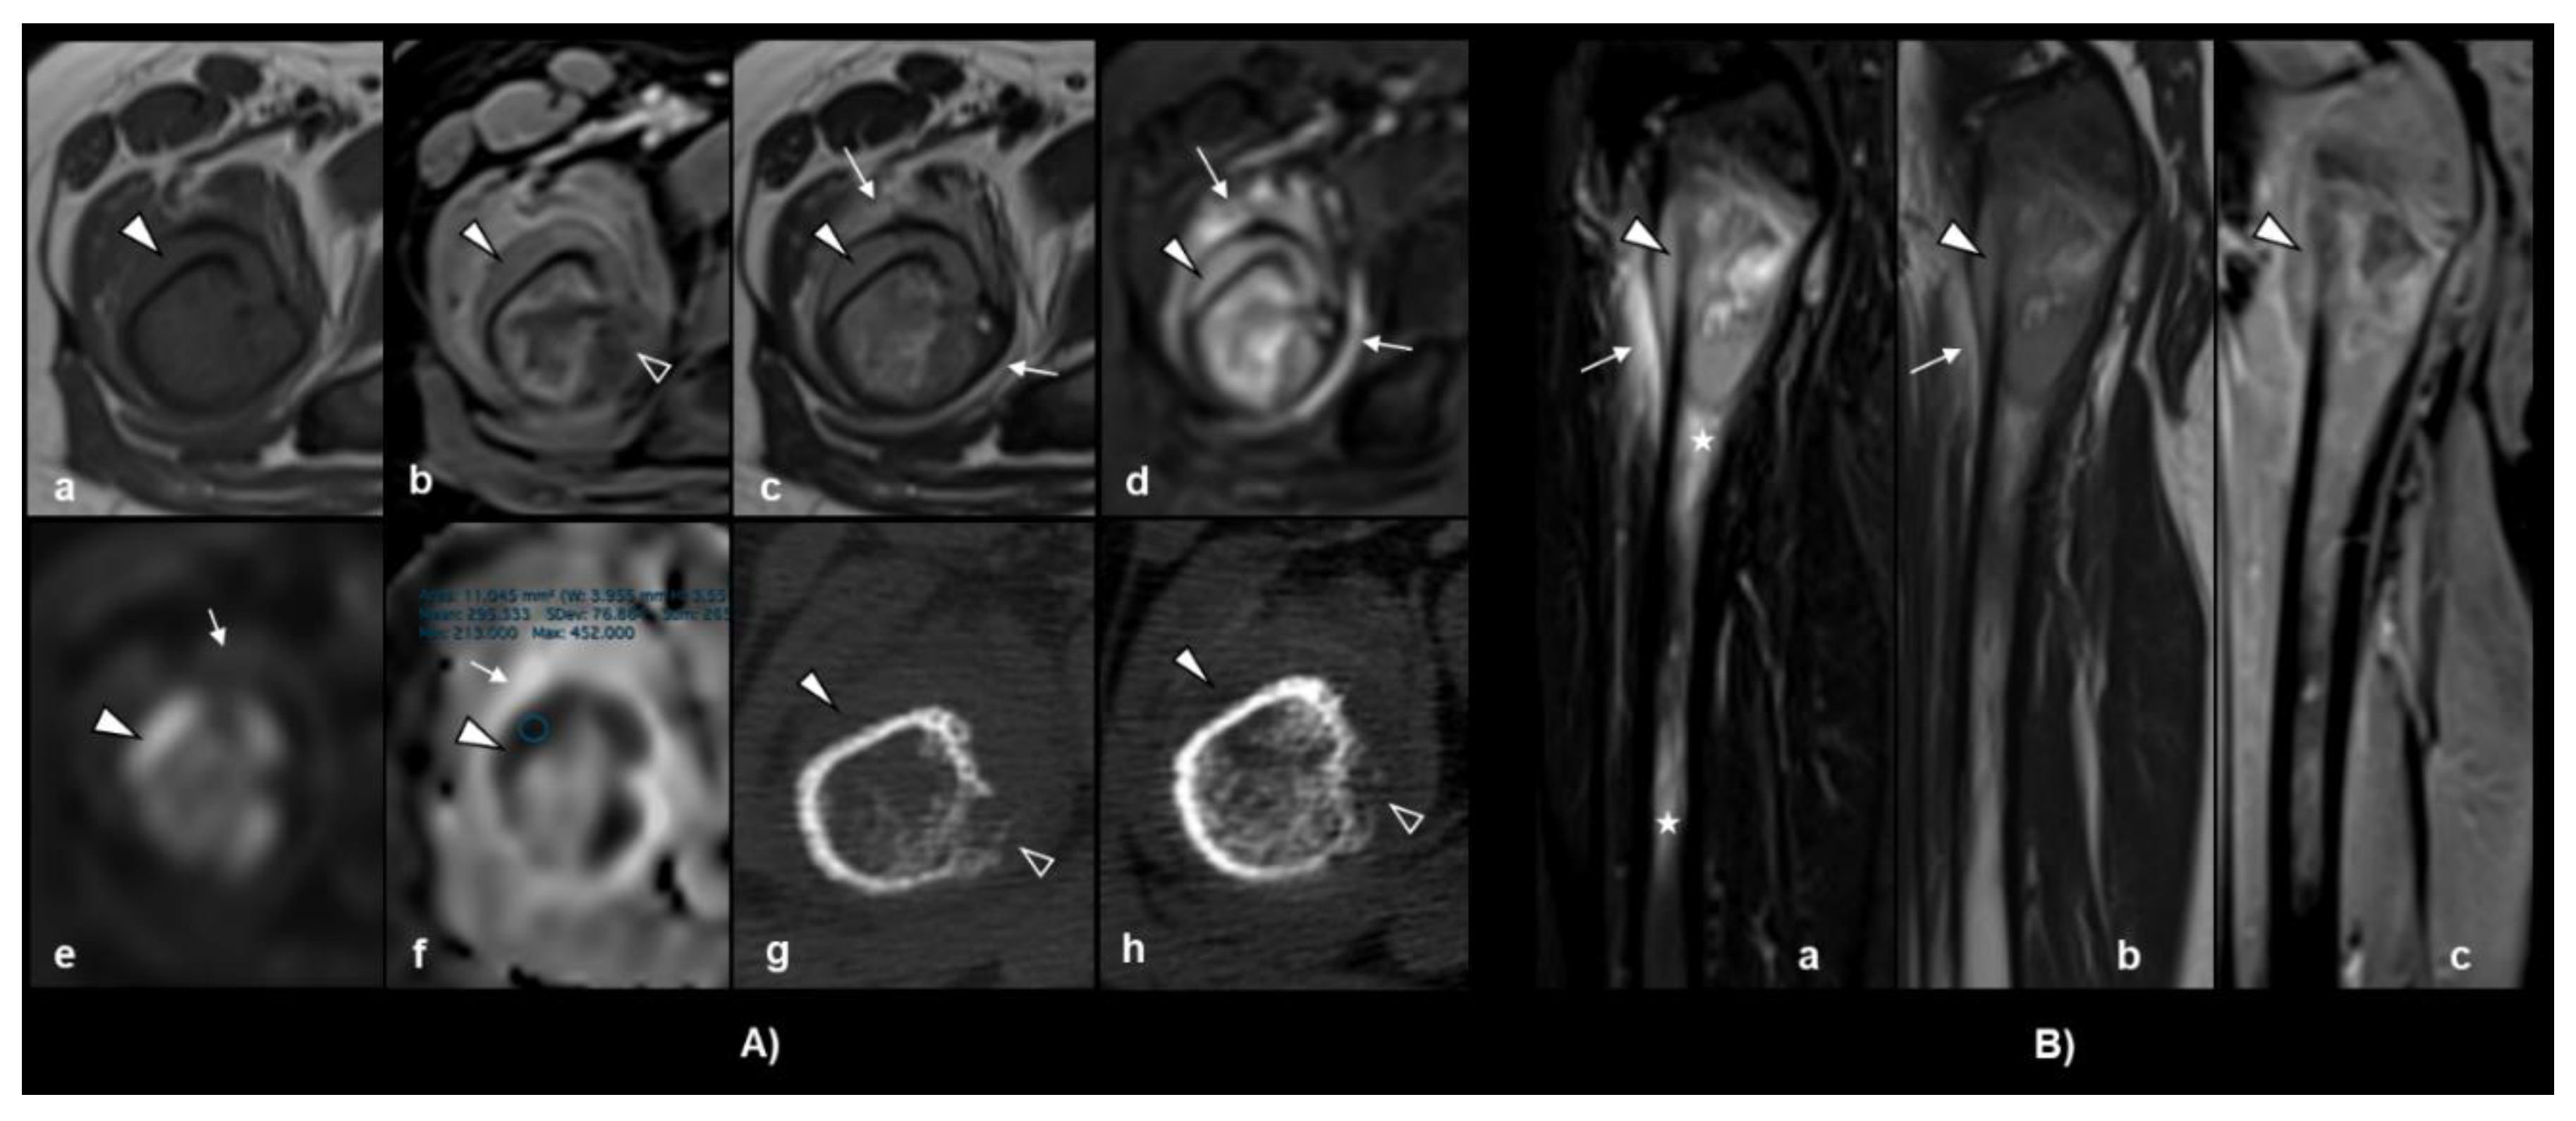

- Meyer, H.J.; Beimler, M.; Borte, G.; Pönisch, W.; Surov, A. Radiological and Clinical Patterns of Myeloid Sarcoma. Radiology and Oncology 2019, 53, 213-213. [CrossRef]

- Roberts, A.S.; Shetty, A.S.; Mellnick, V.M.; Pickhardt, P.J.; Bhalla, S.; Menias, C.O. Extramedullary haematopoiesis: radiological imaging features. Clin Radiol 2016, 71, 807-814. [CrossRef]